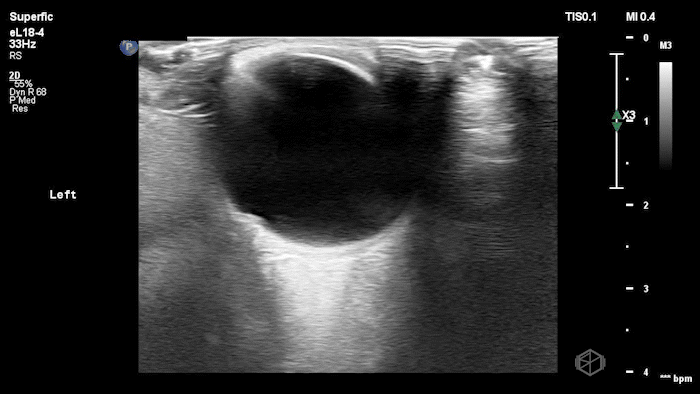

05 - What is being examined and what is the diagnosis?

Phlebitis (no thrombus present to make it thrombophlebitis)